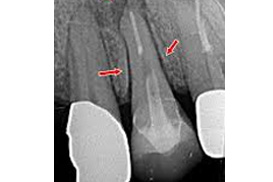

レントゲン写真内の歯根膜腔の拡大

歯の根を覆っている歯根膜の部屋が大きくなります。